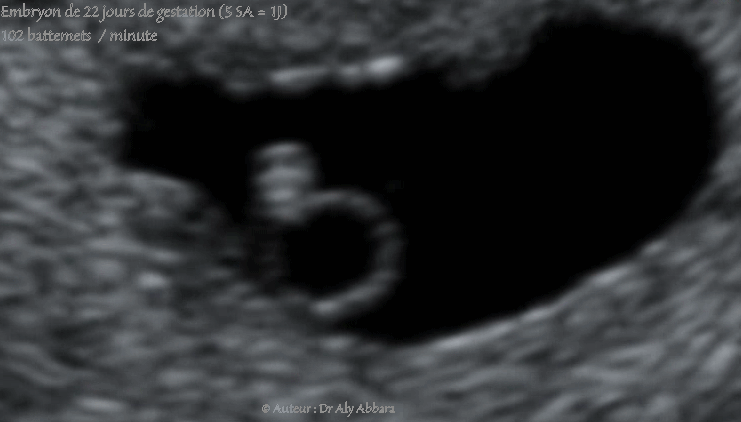

Images échographiques cardiaques montrant les premiers battements cardiaques chez un embryon âgés de 22 jours de gestation (soit cinq semaines d'aménorrhée et un jour).

La longueur crânio-caudale (LCC) = 2,45 mm

La fréquence cardiaque calculée = 102 battements/minute.

En embryologie : au cour de la 4e semaine de grossesse, le cœur commence à battre au jour 22, et le sang se met à circuler dans l'embryon au jour 24.